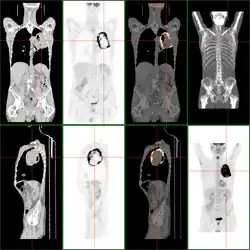

Nekrose im Inneren eines großen Bronchialtumors in der FDG-PET/CT-Darstellung